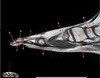

(178 cards)

1

Q

What is letter A?

A

SUPRASPINATUS TENDON

2

What is letter B?

ACROMION

How well did you know this?

3

CORACOID PROCESS

4

DELTOID MUSCLE